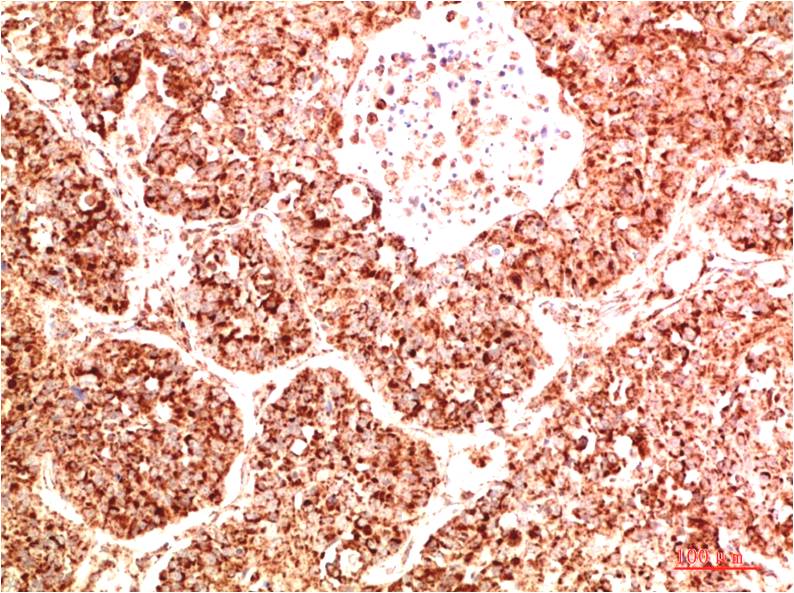

TTR Mouse Monoclonal Antibody(5G9)

Catalog NO.:BE3687

Applications :WB, IHC

Reactivity :H

| Recommended dilutions: | WB 1:1,000-2,000 IHC 1:100-200 |

| Specificity: | The TTR Mouse Monoclonal Antibody can detects endogenous TTR proteins. |